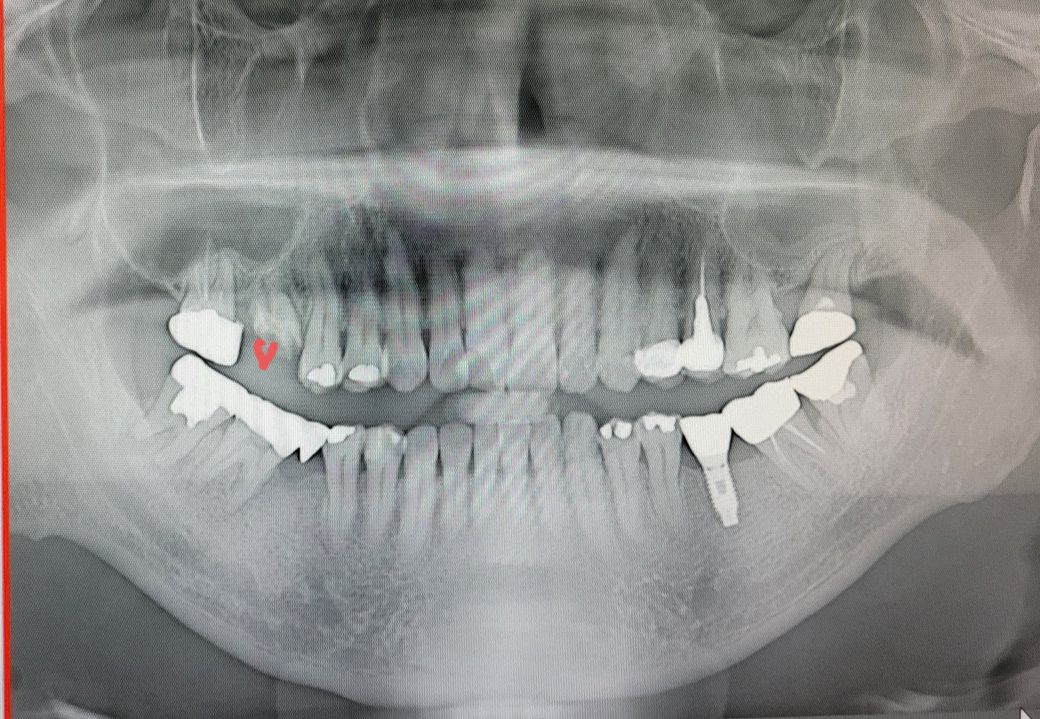

오른쪽 위 어금니가 부러져서 치과를 갔는데 원장님이 임플란트 발치후 상악동 뼈이식과 임플란트 동시식립한다고 하십니다 그리고 매달 엑스레이 보면서 염증 확인 후 6개월 후 보철 하신다는데 괜찮을까요?

저는 발치하고 얼마 지난 후 상악동하고또 얼마지나고 식립하고 보철하고 단계적으로 하는 줄 알았거든요

현재 말씀하시는 부위를 보아 치아 상태가 매우 좋지 않아 발치가 필요해보입니다. 현재 사진으로 정확히 보이지 않지만 염증 등이 있을 가능성도 있어 보입니다.

이러한 경우 보통 발치 이후에 치조골이 충분히 회복되고 난 이후에 임플란트 시술을 계획하기도 하지만 치조골이 너무 부족하다만 발치 즉시 상악동거상술을 시행하고 임플란트를 식립하는 경우도 있습니다.

CT없이 엑스레이만 보고 정확한 답변을 드리기는 어렵겠습니다만, 보여주신 파노라마 엑스레이 상의 잔존골 수준 정도면 발치후 동시식립이 가능한 수준으로 보입니다. 너무 걱정하지 않으셔도 되겠습니다.